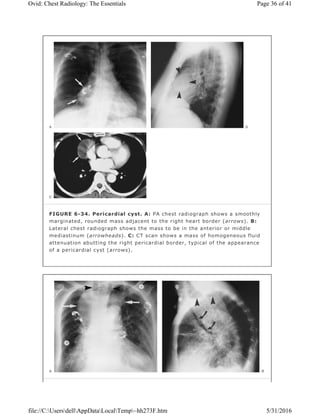

FIGURE 6-34. Pericardial cyst. A: PA chest radiograph shows a smoothly

of a pericardial cyst (arrows).

the diagnosis. Pericardial cysts arise most frequently in the right cardiophrenic

cysts typically contact the heart, diaphragm, and anterior chest wall (Fig. 6-33).

The majority are sharply marginated, somewhat triangular, and of near-water

attenuation on CT scans (Fig. 6-34).